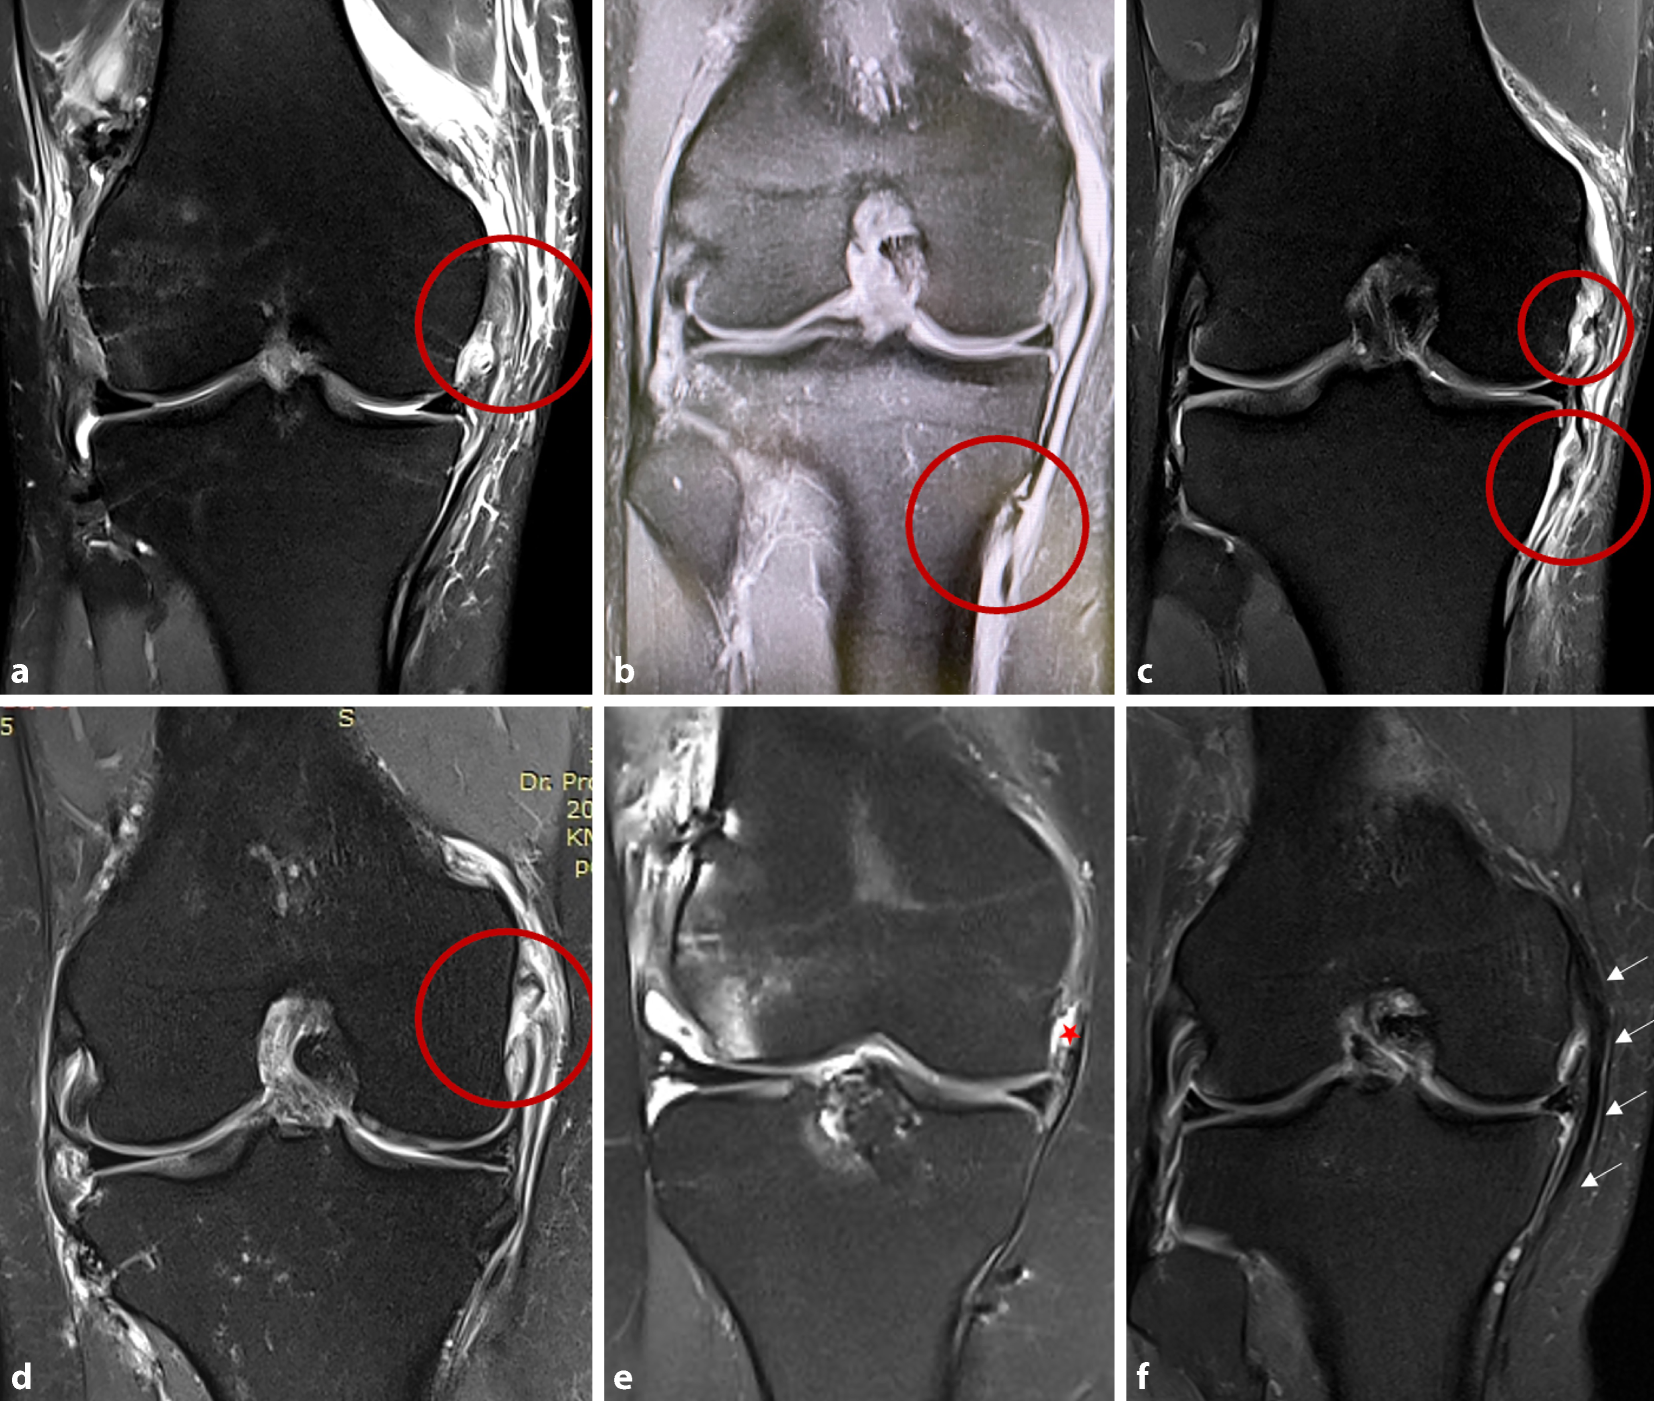

Abb. 3

Magnetresonanztomographie (MRT) der unterschiedlichen Verletzungsmuster in koronarer STIR-Sequenz (Short-Tau Inversion Recovery). a Femorale Avulsion von oberflächlichem (sMCL) und tiefem Seitenband (dMCL). b Isolierte distale Avulsion des sMCL bei intaktem dMCL. c Proximale Avulsion des dMCL und Stener-Läsion des sMCL. d Proximale ansatznahe intraligamentäre Ruptur von dMCL und sMCL. a–d Die Verletzungslokalisation ist jeweils durch einen roten Kreis hervorgehoben. e Chronische proximale dMCL- und sMCL-Instabilität (roter Stern Defekt). f Chronische distale sMCL-Instabilität mit verdicktem sMCL und herabgesetzter Bandspannung

Die meisten medialen Kapselbandverletzungen heilen konservativ mit guten klinischen Ergebnissen aus. Allerdings besteht bei höhergradigen Verletzungen, Dislokationen der Bandstümpfe (z. B. distale Rupturen des sMCL mit „Stener-like lesion“; [8]) oder multiligamentären Verletzungen die Gefahr einer residuellen Instabilität [3, 7]. Diese gilt es, durch operative Versorgung der akuten Verletzung zu vermeiden bzw. in der chronischen Situation zu adressieren. Zur differenzierten Indikationsstellung für eine Operation bedarf es einer genauen Analyse der Rupturform in der Magnetresonanztomographie (MRT; Abb. 3) und der Instabilität im Rahmen der klinischen Untersuchung.